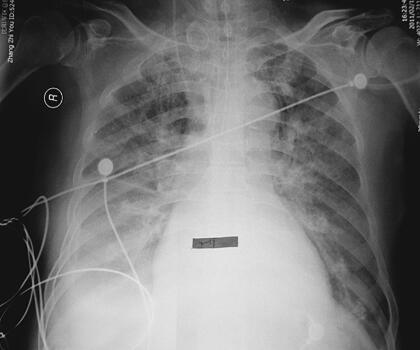

患者,男性,87岁。急性起病,主因“劳累后胸闷、气短2天,加重伴咳嗽、咳痰1天”于2011年2月18日收入急诊监护室。患者于2011年2月16日劳累后出现胸闷、气短,伴咳嗽、咳黄痰,可平卧,偶有夜间憋醒,休息后症状缓解,翌日劳累后再次出现上述症状,无心前区疼痛,无发热、寒战,无恶心、呕吐,无尿少,就诊于笔者医院,进行心脏超声检查:EF 40%,冠心病、心肌梗死表现、心功能减低,考虑心尖部室壁瘤形成,二尖瓣、三尖瓣及主动脉瓣反流(轻度);腹部超声:双侧胸腔积液,少量心包积液;双肺CT(图1):双侧胸腔积液,心胸比例> 0.5;院第2天胸片见图2。血液分析:白细胞9.34×109/L,中性粒细胞85.5%;心肌酶谱:肌钙蛋白0.144μg/L,磷酸肌酸激酶125U/L,磷酸肌酸激酶同工酶20U/L;B型尿钠肽8326pg/ml。既往史:冠心病病史10余年,自服阿司匹林、复方丹参滴丸、硝酸异山梨醇酯等,2010年7月急性心肌梗死经内科治疗后病情稳定;陈旧性脑梗死病史10余年、胃部分切除史20余年。

图2 入院第2天胸片:双肺渗出,右侧明显